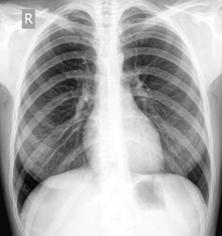

.3 Профилактическое флюорографическое обследование

Метод флюорографического исследования органов грудной клетки является основным методом выявления туберкулеза у подростков. Сроки проведения флюорографических обследований с целью выявления туберкулеза утверждены Постановлением Правительства Российской Федерации от 25.12.2001 г. № 892 «О реализации Федерального Закона «О предупреждении распространения туберкулеза в Российской Федерации».

Все здоровые подростки (с 15 лет) подлежат профилактическим флюорографическим обследованиям не реже одного раза в год.

Основным способом выявления туберкулеза у взрослых и подростков является лучевой метод исследования (флюорография), с применением которого выявлено 95,4% и 72,8% больных активным туберкулезом соответственно. Среди всех впервые взятых на учет больных ТОД выявлено методом флюорографии 56,2%, среди выявленных при массовых осмотрах - 89,3%.